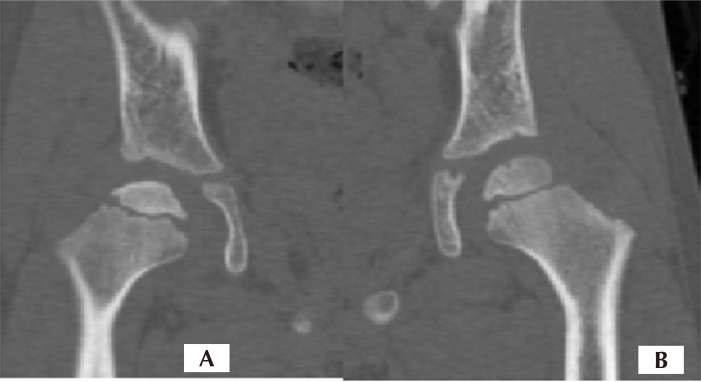

Materials and methods: This case study was based on a simulation analysis. Computed tomography scan images of a subject with Perthes disease were used to create a three-dimensional model of the hip joint on both the normal and Perthes sides. In addition, modeling of the blood vessels of the femoral head, including the foveolar and retinacular arteries, was performed during this study.